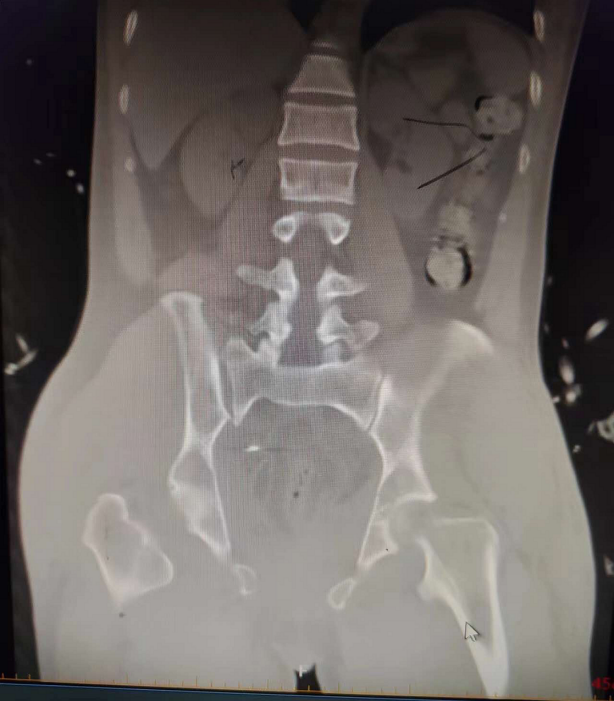

该患者入院诊断:失血性休克,骨盆骨折,膀胱尿道损伤,胸部闭合伤并肋骨多发骨折,双侧足跟骨开放性骨折。入院经急诊创伤中心诊治转入ICU,并急诊行介入血管栓塞、剖腹探查尿道修补手术,病情稳定后转入骨科处理骨盆骨折情况。在该院骨科主任张卫、副主任吴贵勇的组织带领下,骨科创伤团队经过严谨细致的术前讨论和评估,为患者制定个性化微创手术方案。

CT影像显示骨盆骨折情况

因患者骨盆环稳定性完全破坏且尿道损伤已行过开放手术治疗,后续针对骨盆骨折问题,故选择微创手术,减轻患者创伤疼痛,术中行骨盆闭合复位徒手经皮耻骨支逆行通道螺钉内固定技术,骨盆闭合复位infix微创固定技术,骶髂关节不稳闭合复位通道螺钉固定技术。此三种手术方式同时运用在同一个患者上,操作难度极大,风险系数极高,对手术医生有极高的理论、经验及操作要求。手术圆满成功,患者伤口缝合面小,现患者正接受系统的康复功能训练。